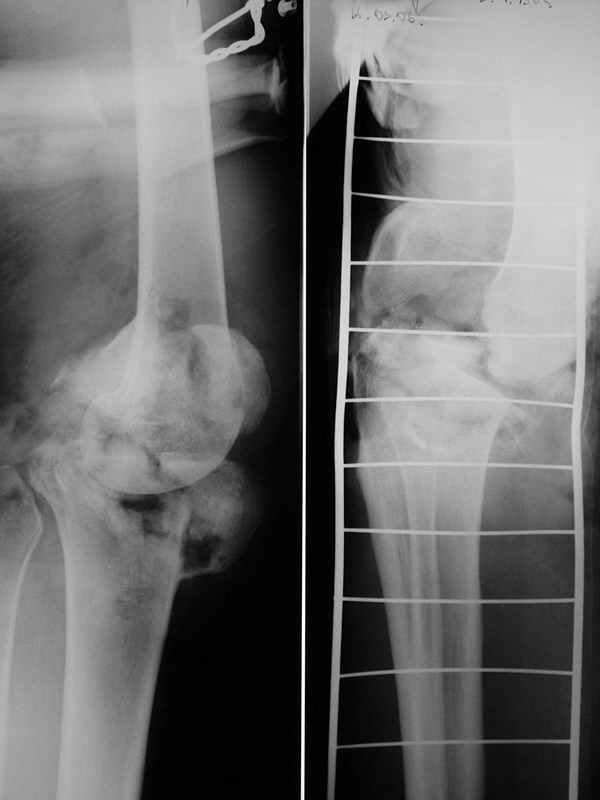

Больной 48 лет, соматически здоров, около 3 недель назад получил тяжелый открытый перелом внутренних мыщелков бедра и большеберцовой кости. Травма производственная - наехал бульдозер.

При поступлении - травматический шок 2 ст. При ревизии раны - отсутствие внутреннего мыщелка бедра, перелом внутреннего мыщелка б/б кости, нестабильность коленного сустава. Повреждений магистральных сосудов и нервов нет. Рваная лоскутная рана по внутренней поверхности колена.Выполнен адаптационный остесинтез остатков кости спицами и мостовидная трансартикулярная фиксация стержневым аппаратом внешней фиксации. Наводящие швы, частично - пластика по Хохутову.Сейчас раны заживают (местами с небольшими некрозиками, но в целом неплохо), встает вопрос о втором этапе лечения. Напрашивается вроде артродез коленного сустава.

Но на контрольных снимках он (внутренний мыщелом) где-то ссзади

Ложе готовить само собой надо,но как быть со спицами?Ведь после некрэктомий железо может оказаться "на улице",верно?Кроме того,допустим рану закроем,все зажило,а дальше?Суставу по-моему,извините,хана!И еще не могу понять,что это на прямом снимке внутренний мыщелок большеберца как-то странно стоит,а на боковом сзади кусок бедра?или что это?Кто разобрался напишите pls.И еще,а нет ли в полости того,что осталось от колена свободных кусков?

1. То, что вы видте на рентгенограммах это к сожалению (моему тоже) не внутренний мыщелок бедра, а лишь "чешуя" - останки его метафиза. Внутренний мыщелок большеберцовой кости действительно смещен, каюсь, во время операции показалось неплохо, а контрольный снимок выполнял уже в реанимации. Учтывая имеющиеся сомнения, в течение недели выполним КТ - снимки представлю.